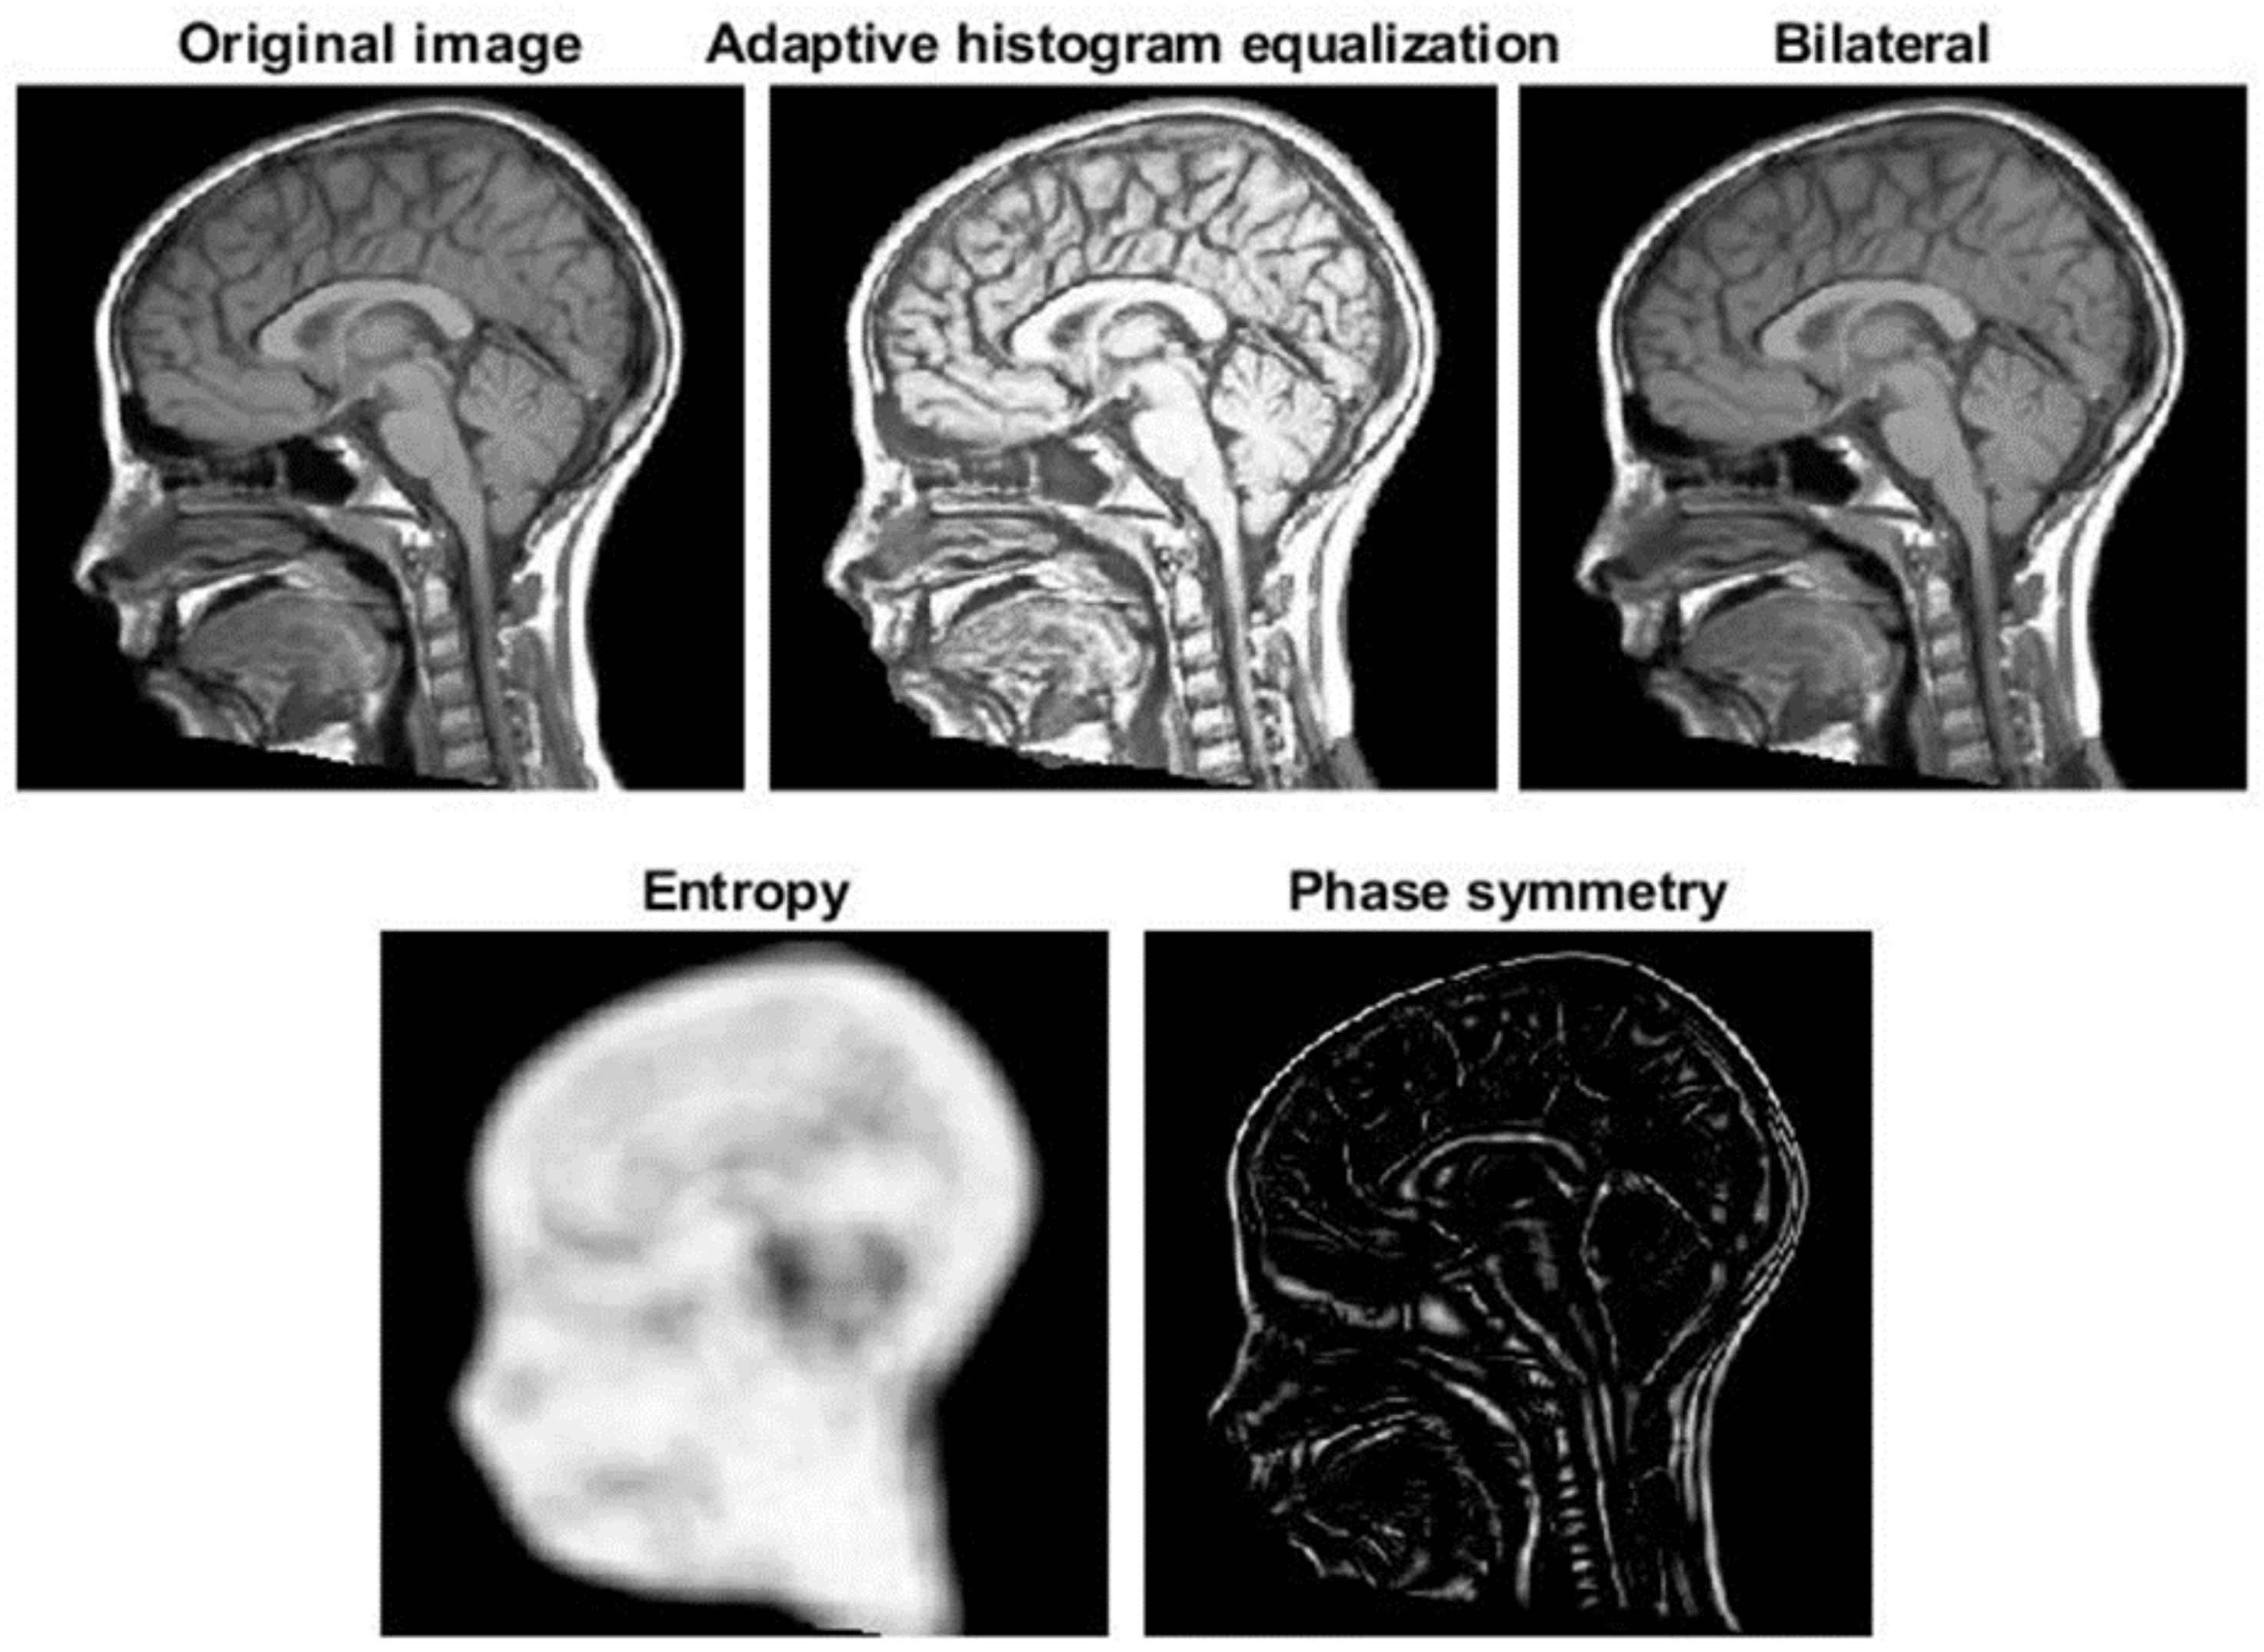

:1. Introduction

2.2. Registration

2.2.1. Balanced Multi-Image Demons

2.2.2. Correction by Active Contour